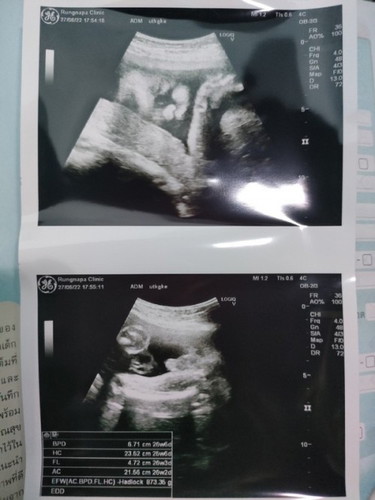

ลูกกลับหัว

ท้อง 25w+6 หมอลงในสมุดชมพูว่าน้องกลับหัวแล้ว เหมือนจะเร็วไปแต่ก็ไม่เห็นหมอว่าอะไรค่ะ แม่ๆน้องกลับหัวกันตอนกี่สัปดาห์ค่ะ